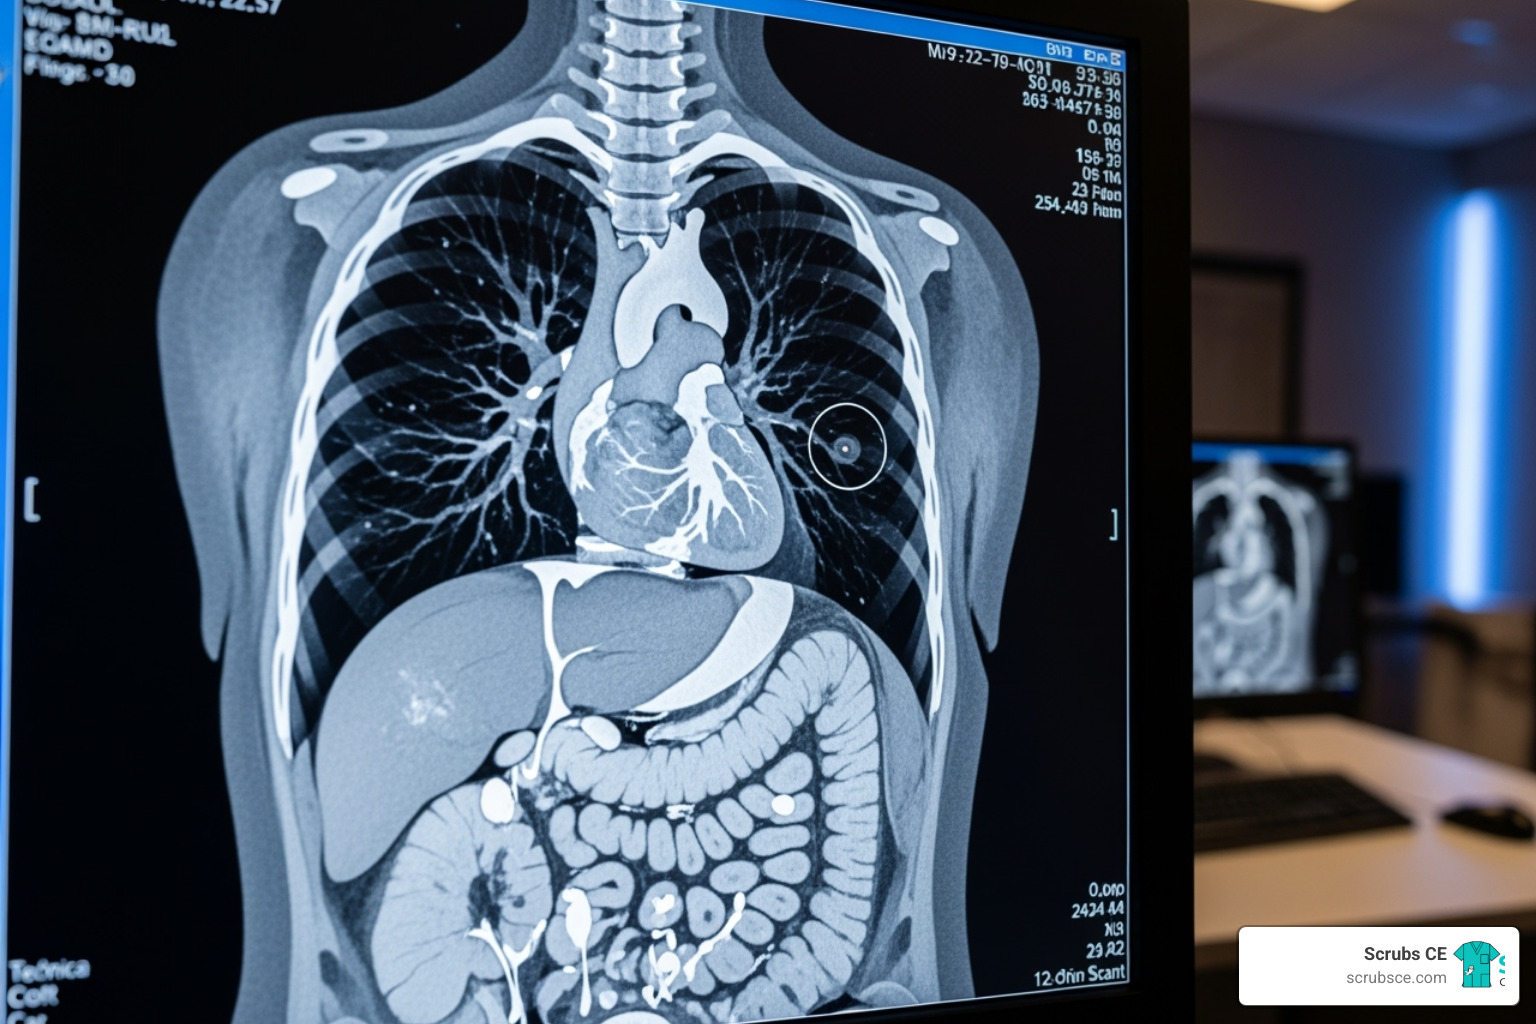

Computed tomography uses a series of x-ray images to create detailed cross-sectional “slices” of the body, which can be digitally stacked into 3D views. As CT technology evolves with innovations like dual-energy scanning and AI, continuing education is vital for delivering better patient care and maximizing career potential—not just for checking licensure boxes.

Image Formation & Evaluation courses teach you to optimize image quality by working with Hounsfield Units, windowing, resolution, and artifact identification. Understanding your PACS (Picture Archiving and Communication System) is also covered.

Sectional Anatomy courses are essential for accurate patient positioning and recognizing anatomical variations.

When it comes to specific procedures, the options get really interesting. Cardiac CT courses focus on imaging the heart, as detailed in our Cardiac and Vascular Computed Tomography course. CT Angiography courses explore imaging blood vessels. You’ll also find specialized courses for abdomen & pelvis, head and spine imaging, musculoskeletal applications, and chest procedures.